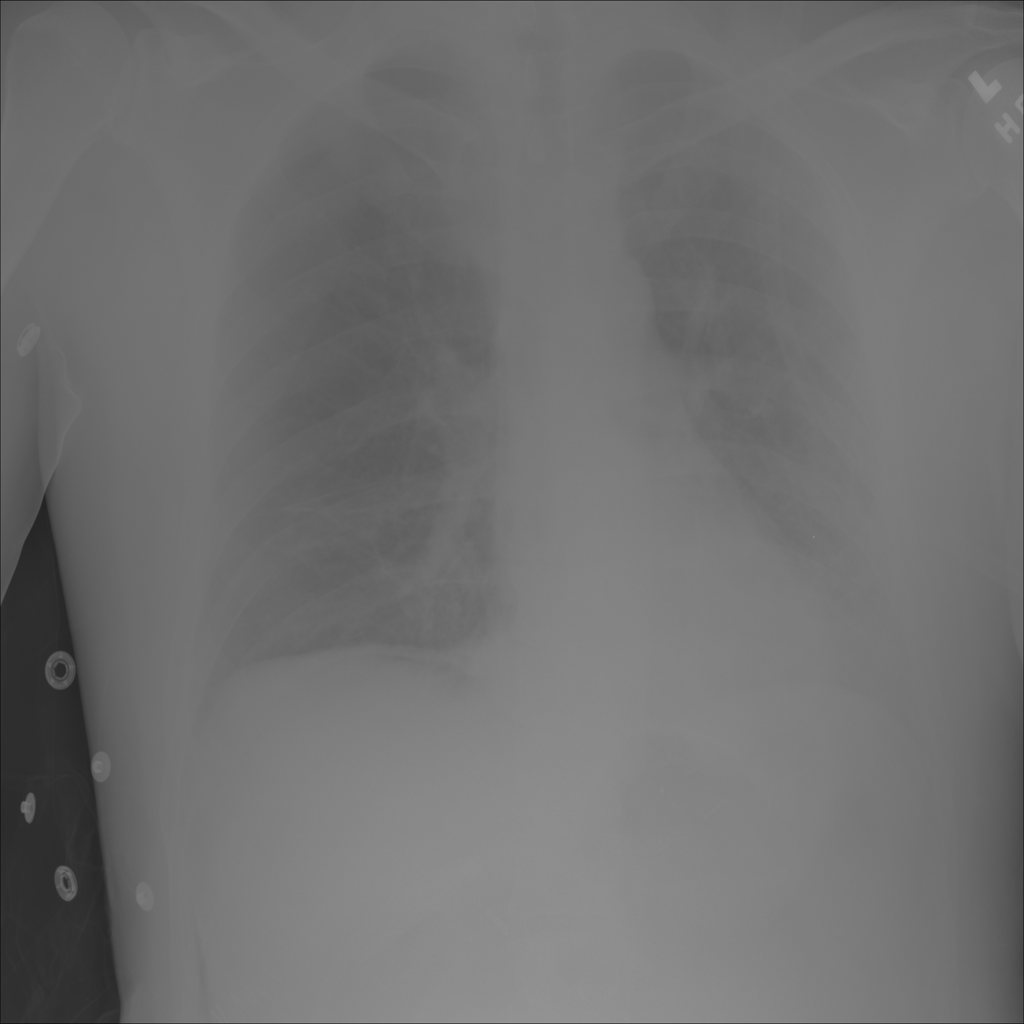

PAT-E066 · IMG-010Fibrosis

PAT-E066 · IMG-010

PA